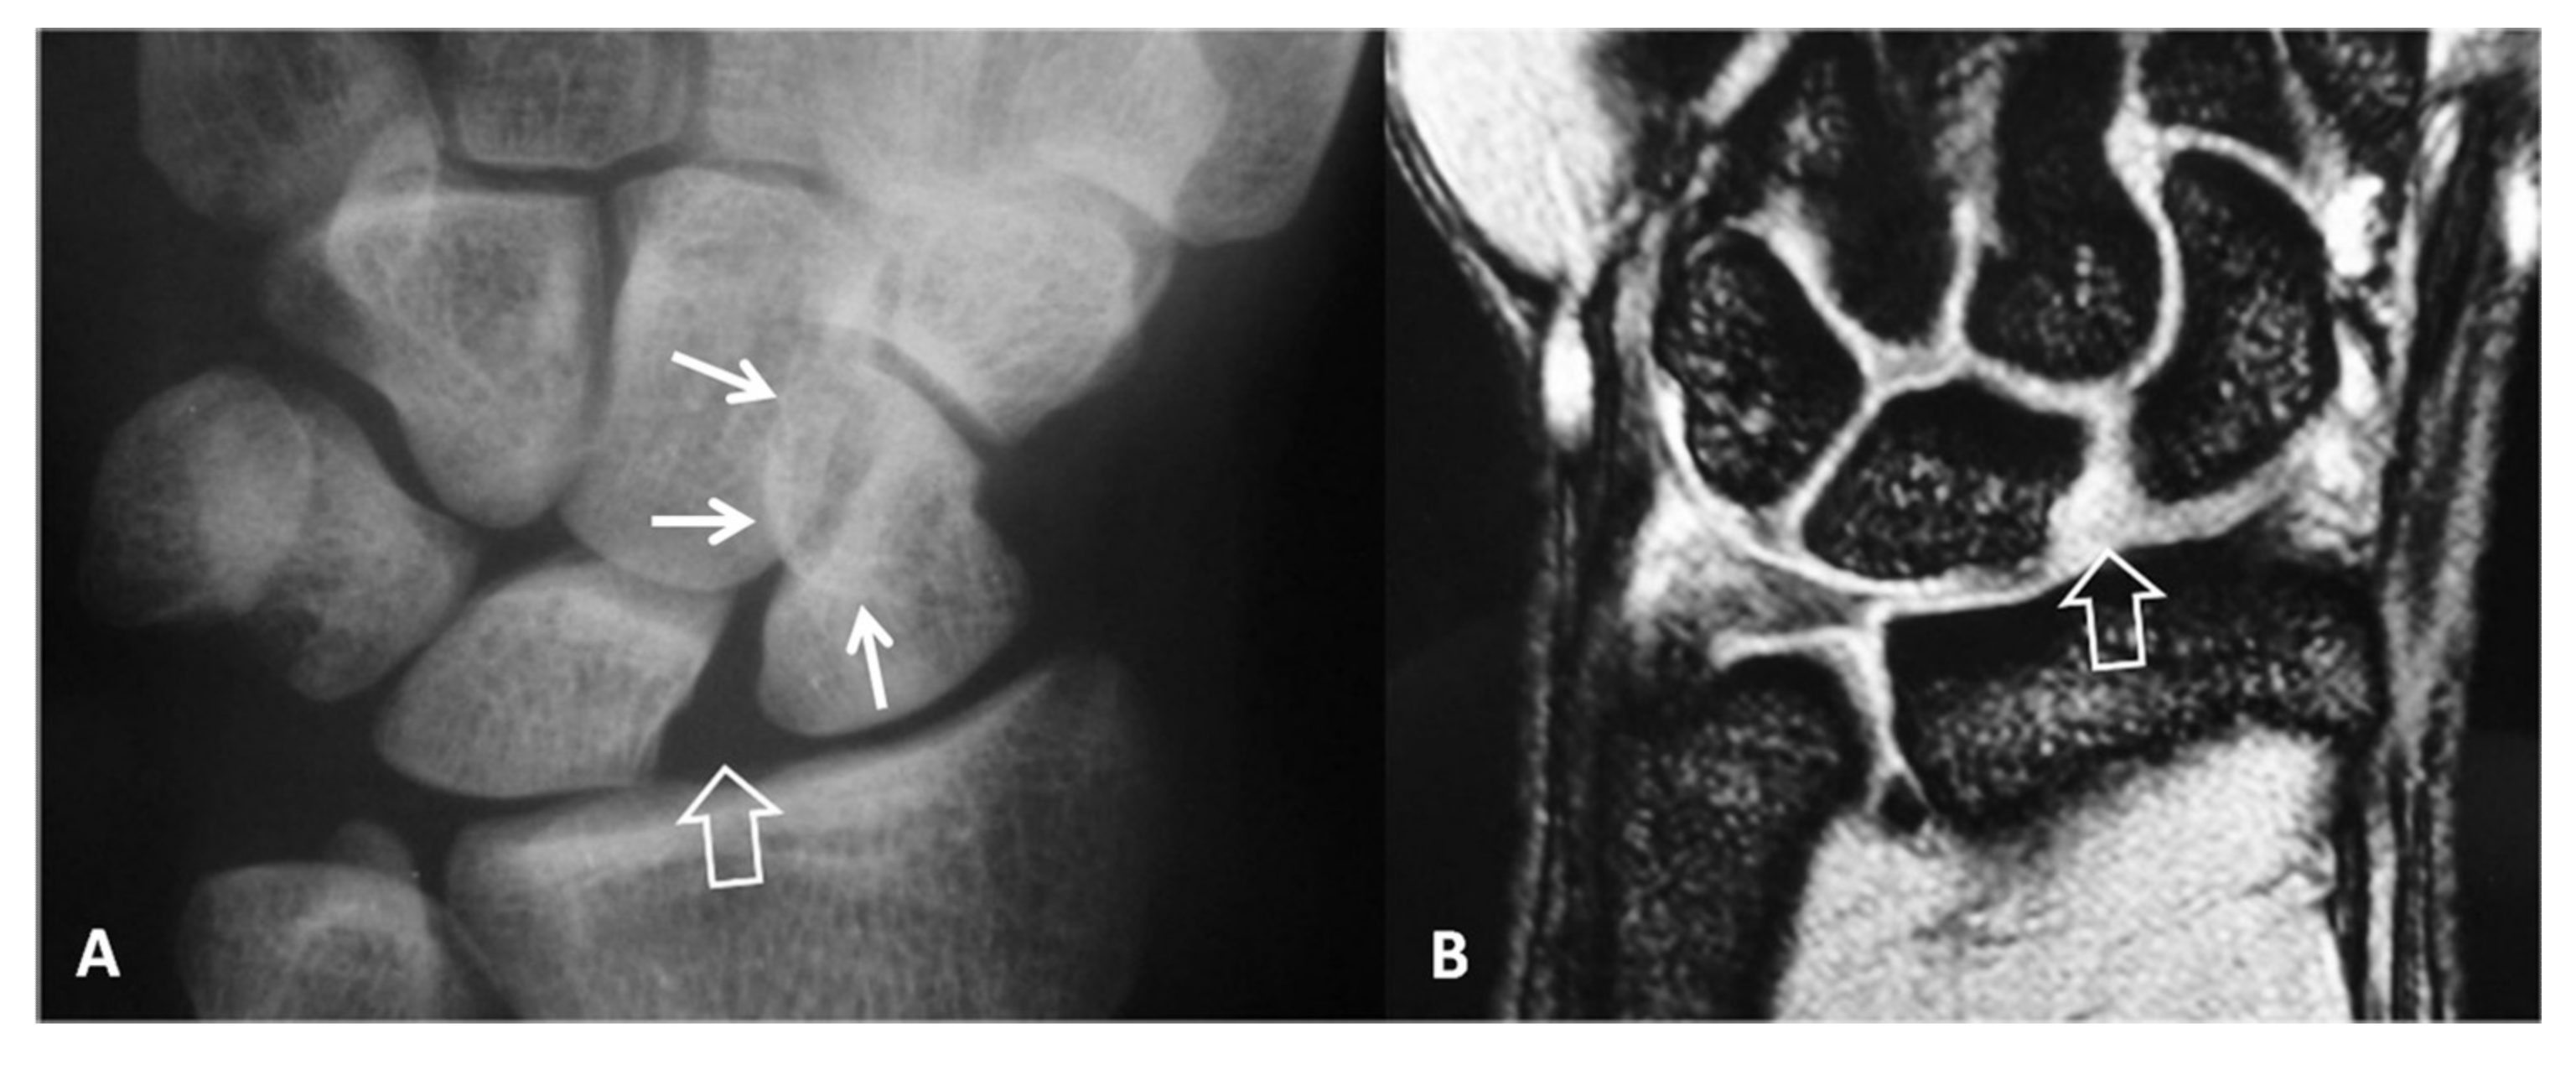

Figure 1.

A 23-year-old male patient with a history of a scaphoid fracture 1 year prior to current imaging. PA radiograph showing pseudarthrosis (arrow), proximal pole osteosclerosis in keeping with osteonecrosis (open arrow) and cyst formation on both sides of the previous fracture (short arrows). The radioscaphoid joint space is intact.

Figure 2.

A 34-year-old orthopedic surgeon, practicing in Boxing, presents with 3-month period of pain and limited range of motion.(A) PA radiograph showing the increased scapholutane distance suggesting scapholunate ligament rupture (open arrow). The finding is often called as the “Thery-Thomas” sing, after the famous actor teeth appearance. The “signet ring” sign is also evident due to the foreshortening of the scaphoid (arrows). (B) Coronal T2* MR image showing the absence of the low signal intensity membranous ligament (open arrow) in keeping with scapholunate ligament tear. The radioscaphoid joint space is intact.